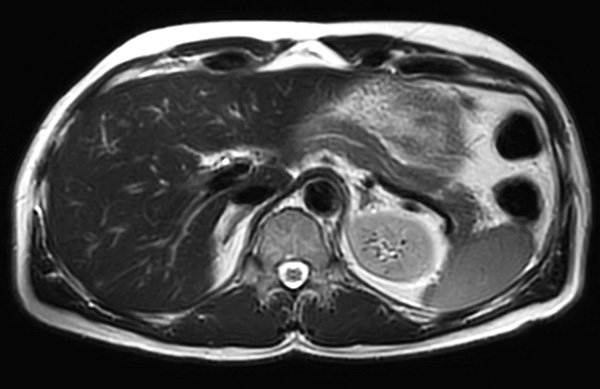

Axial T2w TSE